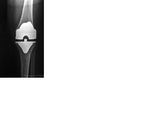

جراحة إستبدال الركبة يمكن أن تكون إستبدالا جزئياً أو إستبدال الركبة بالكامل.[2] في الإستبدال بصفة عامة تتكون من جراحة استبدال الأسطح المريضة أو التالفة للركبة بأجزاء معدنية أو بلاستيكية على شكل مكونات تسمح باستمرار حركة الركبة.

لاحقا، يتم تعديل أسطح المفصل بحيث تستطيع احتواء المفصل الاصطناعي المركب من البلاستيك والمعدن. يتم الصاق المفصل الاصطناعي بعظمة الفخذ، الساق والرضفة، بواسطة مادة ملاطية أو مادة أخرى، تستعمل كمادة لاصقة فسيولوجية. من ثم، يتم تثبيت المفصل الاصطناعي إلى عضلات الركبة والأربطة الداعمة للمفصل، من أجل الحصول على أداء حركي في المفصل بشكل مماثل للوضع الطبيعي. يتكون الجزء الملتصق بعظمة الفخذ من معدن صلب وأملس، والذي يستطيع تحمل أوزان ثقيلة. يتم تغطية المفصل بضمادة مرنة.